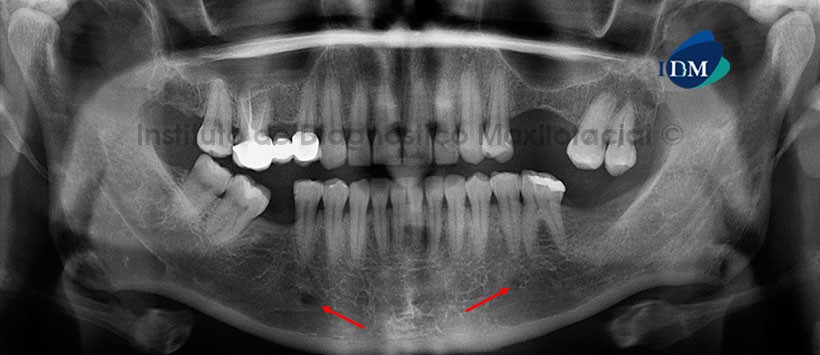

Paciente femenino de 46 años de edad que es referida para la evaluación previa a la colocación de implantes dentales. En la radiografía panorámica se evidencia la mineralización de los procesos estilohioideos, neumatización alveolar de los senos maxilares, edentulismo parcial, puente protésico desadaptado a nivel de las piezas posteriores del maxilar superior derecho, lesiones de caries y restauraciones coronarias (Fig. 1). No se evidencia alguna alteración aparente del tejido óseo.